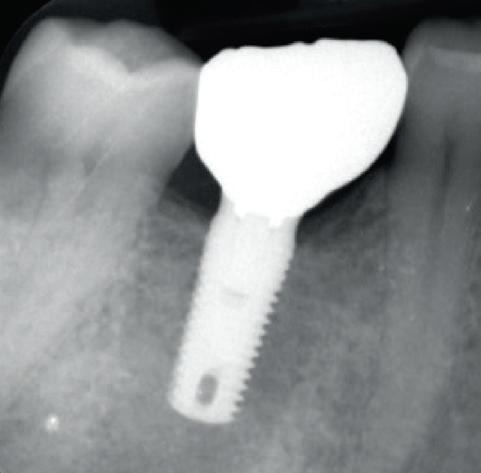

Each year, millions of people get dental implants as a longterm, natural-looking fix for missing teeth. But traditional implants don’t fully mimic real teeth.

Researchers from Tufts University School of Dental Medicine and Tufts University School of Medicine recently described a new approach to dental implants that could better replicate how natural teeth feel and function. Their study, published in Scientific Reports, shows early success with both a “smart” implant and a new gentler surgical technique in rodents.

“Natural teeth connect to the jawbone through soft tissue rich in nerves, which help sense pressure and texture and guide how we chew and speak. Implants lack that sensory feedback,” said Jake Jinkun Chen, DI09, a professor of periodontology and director of the Division of Oral Biology at the School of Dental Medicine and the senior author on the study.

Traditional dental implants use a titanium post that fuses directly to the jawbone to support a ceramic crown, and the surgery often cuts or damages nearby nerves. To tie these inert pieces of metal into the body’s sensory system, the Tufts team developed an implant wrapped in an innovative biodegradable coating. This coating contains stem cells and a special protein that helps them multiply and turn into nerve tissue. As the coating dissolves during the healing process, it releases the stem cells and protein, fueling the growth of new nerve tissue around the implant.

The coating also contains tiny, rubbery particles that act like memory foam. Compressed so that the implant is smaller than the missing tooth when it’s first inserted, these nanofibers gently expand once in place until the implant snugly fits the socket. This allows for a new minimally invasive procedure that preserves existing nerve endings in the tissue around the implant.